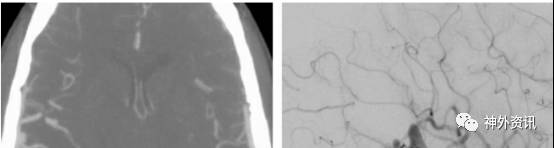

图4. 简单的颞叶外侧面AVMs。这是位于颞叶下方颞下回的病变,P2段分支颞后动脉于病灶后缘进入并参与供血。注意向后方引流的粗大引流静脉(见侧位和正位的颈内动脉造影)。主要的供血来源于颞叶上动脉。对于优势半球颞叶后方的病变,需要注意保留Wernicke语言区,它位于距颞极约5厘米的颞中、颞上回。

笔者不建议术前利用功能磁共振标记(语言功能区)或术中唤醒下开颅切除任何AVMs。通过脑沟间入路可以达到病灶的完整切除,永久性语言功能损伤的风险很低。